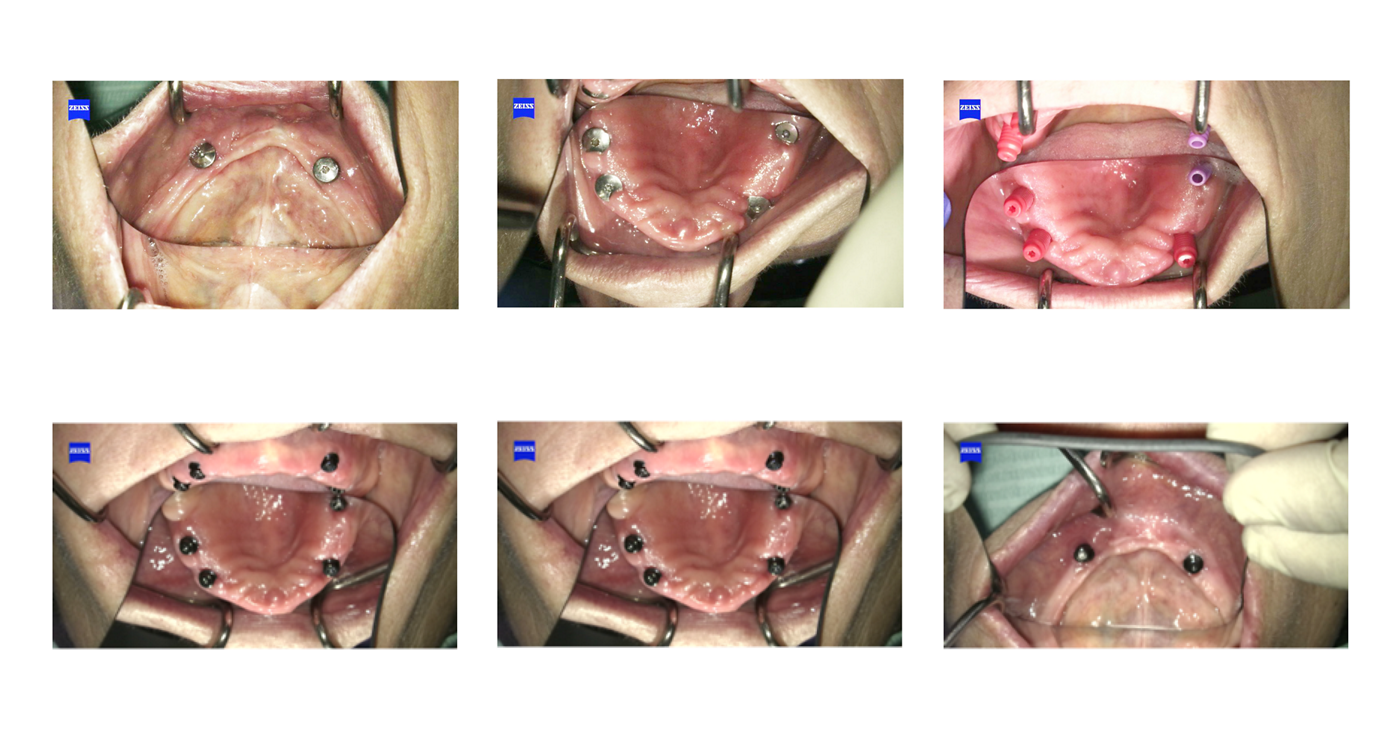

Full thickness flaps were raised in the Maxilla and the uneven ridge was flattened. Straumann 4.1 Regular Neck Standard implants were placed in the canine and 2nd premolar/1st molar sites and a Straumann 4.8mm Bone Level Tapered Implant was placed in the 15/16 due to the need for additional insertion torque.

In the mandible, extensive flattening of the alveolar ridge was carried out to gain enough width for implant placement. Straumann Regular Neck Standard implants were placed in the lower canine positions. The left fixture was placed slightly distally as the initial osteotomy resulted in a spinner in the 33 site. Healing caps were placed and the flaps closed

The patients existing F/F was replaced. After 2 months a second stage appointment was carried out with the placement of Straumann Novaloc abutments.

“This was fortuitous, as available bone volume did not allow for parallel placement of all the fixtures. The availability of angled Novaloc abutments was invaluable”

Straumann® Novaloc® abutments were chosen in this case to allow for lack of parallelism. The Novaloc abutments are available in both straight and 15° angulation allowing a 60° implant divergence.

A mixture of 1 and 2mm gingival height straight and angled abutments were placed and torqued to 35Ncm. A pick-up impression was taken and the overdentures were modified to allow attachment to the Novaloc